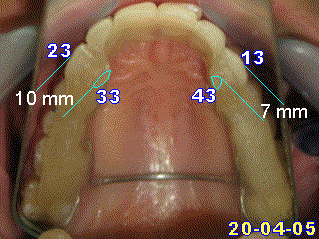

-j'ai mesuré la hauteur faciale inférieure SNaXiPm, elle est parfaite, 48, mésofacial. Et ca , en fixe, les résultats n'auraient pas été aussi bons, l'obtention plus aléatoire.

Je pense que c grace a ton jeu d'ingression.Isaie et Algi pourraient te le confirmer, je ne suis pas assez "calé" la dessus.

- et tres important pour un occlusodontiste, les prévisions de croissance vont vers une normale inclinaison du plan palatin ((8.5) et du plan occlusal (7.5). Et ca c'est le jeu vertical, du a ton action par REIOR GAL.

Dors en paix, occlusion, ton action a permis d'éliminer des facteurs fonctionnels négatifs et de stabiliser des plans importants, necessaires pour éviter l'apparition de récidives apres le traitement multiattaches, qui n'en sera que raccourci!!.